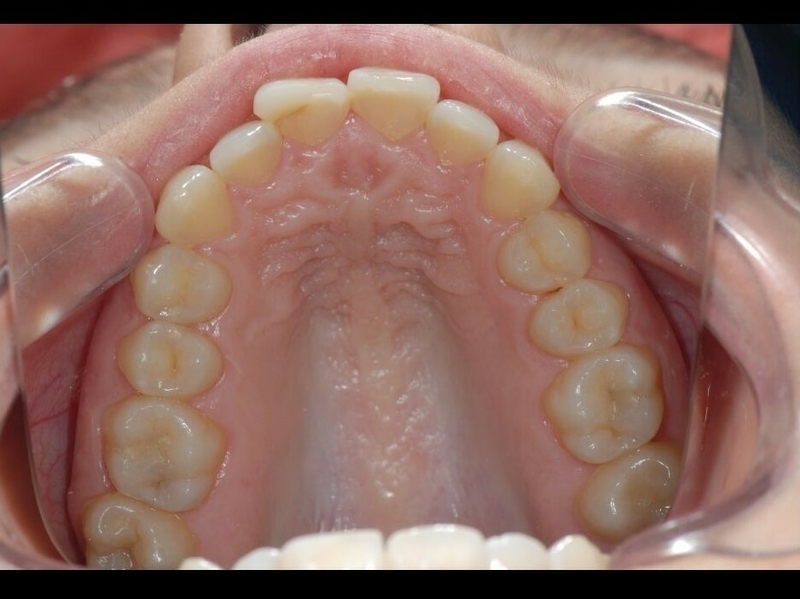

Avant

Après